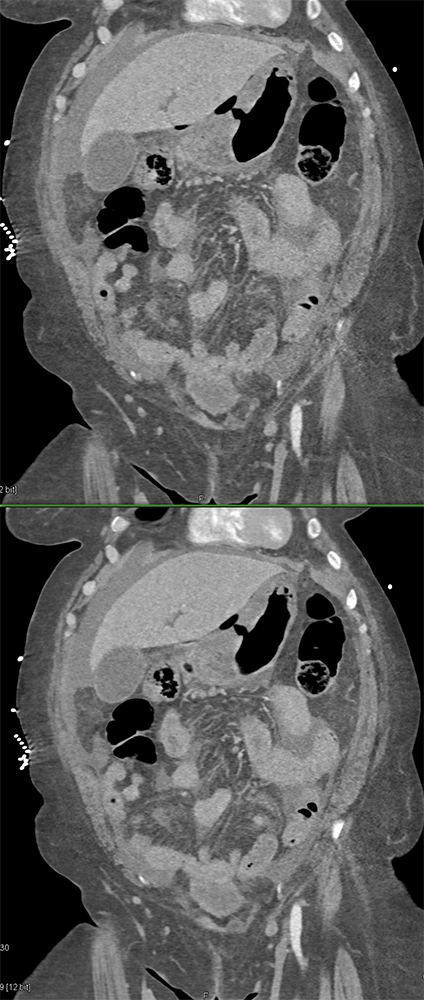

Watermelon stomach (WMS), or gastric antral vascular ectasia (GAVE) ![]() |

“Gastric antral vascular ectasia primanily affects women (9:1 female-to-male ratio) aged 56-76 years, and is associated with liver cirrhosis (37%) and achlorhydnia (35%). The usual symptoms are iron-deficiency anemia and melena due to chronic gastrointestinal bleeding from the dilated, superficial, and easily traumatized vessels. Antrectomy is curative, but endoscopic treatment with heat probes or lasers has shown promise.” Gastric antral vascular ectasia ("watermelon stomach"): radiologic findings. Urban BA, Jones B, Fishman EK, Kern SE, Ravich WJ. Radiology. 1991 Feb;178(2):517-8. |

“In our patient, the findings of prominent mucosal folds extending from the pylonic channel on upper gastrointestinal series and the thickened antral wall on CT scans correlate well with the known pathologic appearance of gastnic antral vascular ectasia. Histologically, antral thickening results from a combination of foveolar and fibromuscular hyperplasia. Grossly, the antral fold prominence appears to result from bunching of the mucosa in the thickened, hypercontractile antrum.” Gastric antral vascular ectasia ("watermelon stomach"): radiologic findings. Urban BA, Jones B, Fishman EK, Kern SE, Ravich WJ. Radiology. 1991 Feb;178(2):517-8. |